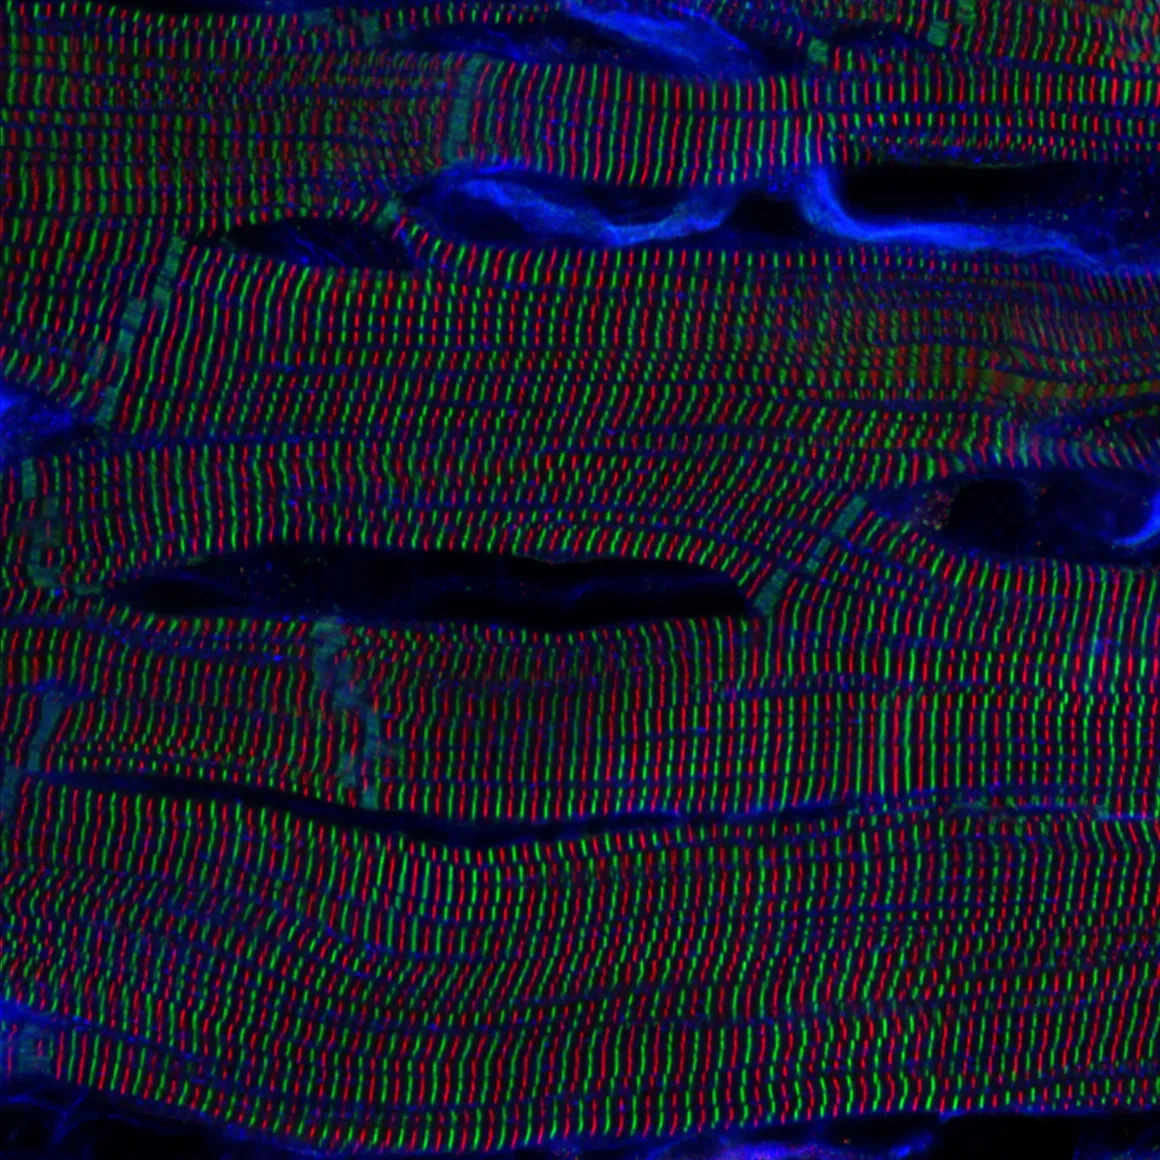

Üç farklı bölgesel kazanan da açıklandı. Almanya’dan Gerd Günther, hindiba bitkisinin polen yapısını gösteren görüntüsüyle EMEA bölgesinde birinci oldu. Amerikalı Igor Siwanowicz, ebegümeci poleninin mikroskobik fotoğrafıyla Amerika kategorisini kazandı. Japonya’dan Kentaro Mochizuki ise sıçan kalbindeki sarkomer yapısını gösteren etkileyici görüntüsüyle Asya-Pasifik bölgesinde birincilik elde etti. Bölgesel kazananların her biri, CX23 dik mikroskop veya SZ61 stereo mikroskop arasında seçim yapabilecek.